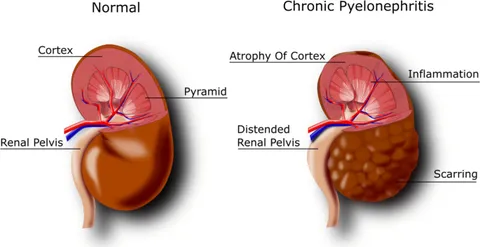

Comparison between Healthy and Damaged Kidneys

A healthy kidney efficiently filters waste and fluids, maintains electrolyte balance, regulates blood pressure, produces beneficial hormones, preserves bone health, and enhances blood circulation. In contrast, a damaged kidney experiences reduced function, leading to waste accumulation, electrolyte imbalance, challenging blood pressure control, hindered hormone secretion, weakened bones, and overall health risks. Early monitoring and management of kidney health are crucial to prevent further damage.

Stage 1: Kidney Health (Stage 1): GFR is normal, but there may be other kidney issues or risk factors present.

Stage 2: Mild Kidney Damage (Stage 2): GFR slightly declines but remains within the normal range, often accompanied by other kidney issues.

Stage 3: Moderate Kidney Damage (Stage 3): GFR further decreases, possibly between 30-59 mL/min/1.73m². This stage may show mild symptoms like fatigue and swelling.

Stage 4: Moderate to Severe Kidney Damage (Stage 4): GFR continues to decline, potentially between 15-29 mL/min/1.73m². More noticeable symptoms might occur, such as anemia and skeletal problems.

Stage 5: Kidney Failure (Stage 5): GFR is very low, below 15 mL/min/1.73m². This is the most severe stage, requiring kidney replacement therapies like dialysis or kidney transplantation.

If your kidneys are already in Stage 5, kidney patches can only alleviate its complications rather than provide a curative effect. For stages above Stage 4, kidney patches can be used to intervene artificially and aid in the recovery of kidney function.